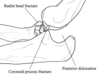

What is the Terrible Triad?

Posterior elbow dislocation with:

- Lateral collateral ligament injury

- Radial head fracture

- Coronoid fracture

Leads to a very unstable elbow and likely to have stiffness, instability, arthrosis. Needs radial head ORIF, LCL reconstruction, coronoid ORI